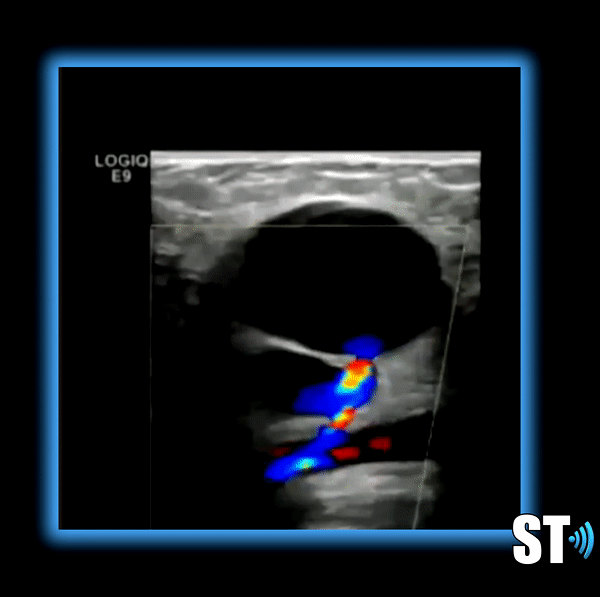

Patients should fast overnight to eliminate excess bowel gas. Scan the patient supine and lateral decubitus. Scan the Aorta in sagittal and transverse including grayscale, color doppler and spectral waveform analysis. Document proximal, mid and distal aorta and bilateral Iliac arteries including anteroposterior measurements.